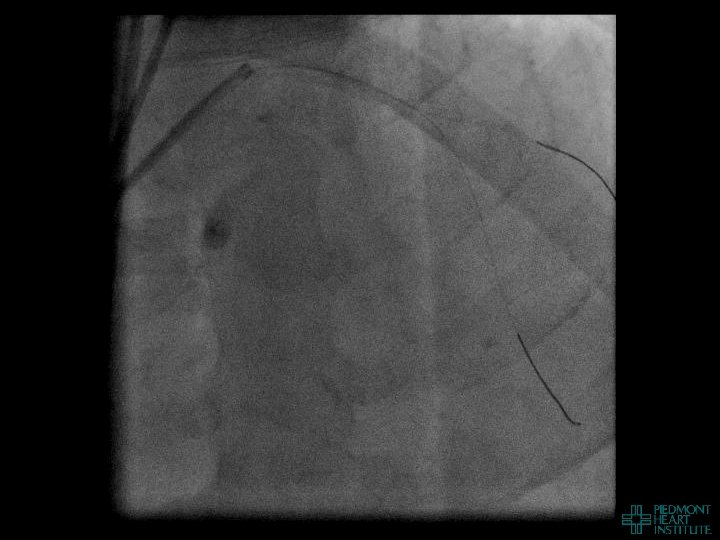

Coronary Perforation Methods of Patient Management • Dual Catheter (‘Ping Pong’) Technique • Prolonged

Coronary Perforation Methods of Patient Management • Dual Catheter (‘Ping Pong’) Technique • Prolonged balloon inflation and covered stents • Reversal of anticoagulation — Know contradictions to protamine sulfate for UFH; Avoid bivalirudin, LMWH — Reserve GP 2 b 3 a inhibition until successful crossing and wire change-out Embolization • — Coil, gelfoam, methacrylate, autologous blood/fat • Microcatheter Occlusion • Confirmation of successful management — Contralateral injection — Right heart catheterization — Echocardiogram — Contrast echocardiography